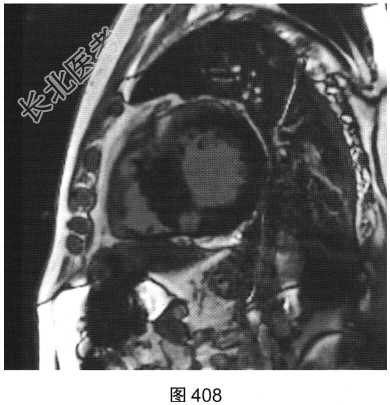

- [材料题] 患者男性,43岁,因“活动后胸痛3年”,外地医院拟诊梗阻性肥厚型心肌病,为明确诊断而转诊本院。

- 简答题3、患者超声心动图检查未能明确诊断,临床申请心脏磁共振检查,如图404~图408所示。患者心脏磁共振检查的异常征象有?